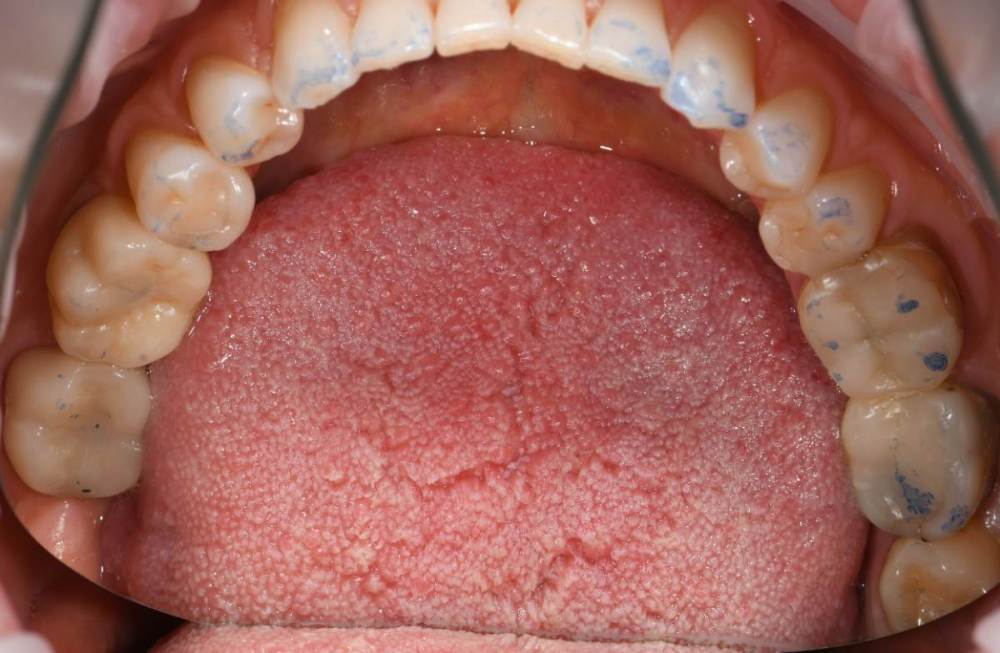

Высылаю фото отпечатков при прикусе , мою искривленную улыбку  панараму 2016 года до имплантации и сейчас. Так же ситуацию с 36.37

DSC_2179.JPG

DSC_2178.JPG

IMG_3345.jpg

IMG_3330.jpg

IMG_3321.JPG